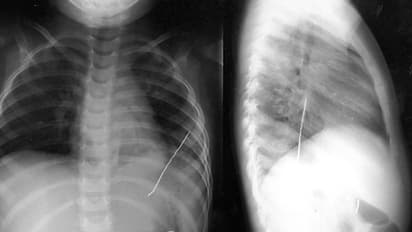

ശിരോവസ്ത്രത്തിൽ കുത്താൻ വേണ്ടി പല്ലിനിടയിൽ കടിച്ചു പിടിച്ച പിൻ അറിയാതെ വിഴുങ്ങുകയായിരുന്നു. ഉടൻ തന്നെ വീട്ടുകാർ പെൺകുട്ടിയെ തൊട്ടടുത്തുളള ആശുപത്രിയിൽ എത്തിച്ചു. തുടർന്ന് എക്സ് റേ എടുക്കുകയും പിൻ ശ്വാസകോശത്തിൽ കുടുങ്ങിയ നിലയിൽ കണ്ടെത്തുകയുമായിരുന്നു. എൻഡോസ്കോപ്പി വഴി പിൻ പുറത്തെടുക്കാൻ ഡോക്ടർമാർ ശ്രമിച്ചെങ്കിലും നടന്നില്ല.

തുടർന്ന് ഗോവയിലെ മൂന്ന് മെഡിക്കൽ കോളേജുകളിലും രണ്ട് സ്വകാര്യ ആശുപത്രികളിലും ചികിത്സയ്ക്കായി പോയിരുന്നെങ്കിലും ഡോക്ടർമാർക്കൊന്നും പെൺകുട്ടിയെ സഹായിക്കാൻ കഴിഞ്ഞില്ല. ശസ്ത്രക്രിയയിലൂടെ പിൻ പുറത്തെടുക്കാമെന്ന് ഡോക്ടർമാർ നിർദ്ദേശിച്ചിരുന്നെങ്കിലും പെൺകുട്ടിയുടെ മാതാപിതാക്കൾ സമ്മതിച്ചില്ല. പിന്നീട് ചെമ്പൂരിലെ സെൻ മൾട്ടിസ്പെഷ്യലിറ്റി ആശുപത്രിയിലെത്തി ബ്രോങ്കോസ്കോപ്പി വഴി പിന് പെൺകുട്ടിയുടെ ശ്വാസകോശത്തിൽനിന്ന് പുറത്തെടുക്കുകയായിരുന്നു.

പിൻ പുറത്തേക്ക് എടുക്കാൻ ഇനിയും വൈകിയിരുന്നെങ്കിൽ ശ്വാസകോശത്തിലേയും കരളിലേയും രക്തക്കുഴലുകൾക്ക് തകരാർ സംഭവിക്കുമായിരുന്നു. കൂടാതെ അണുബാധയ്ക്കും സാധ്യയെറേയായിരുന്നുവെന്ന് ശസ്ത്രക്രിയയ്ക്ക് നേതൃത്വം നൽകിയ ഡോക്ടർ അരവിന്ദ് കെയ്റ്റ് പറഞ്ഞു. എൻഡോസ്കോപ്പി വഴി പിൻ പുറത്തെടുക്കുന്നത് വളരെ അപകടം പിടിച്ചതിനാലാണ് ബ്രോങ്കോസ്കോപ്പി ചെയ്തത്. ഒരാഴ്ചയോളമായി ശ്വാസകോശത്തിലായതിനാൽ പിൻ പുറത്തെടുക്കുമ്പോൾ രക്ത ധമനികൾക്ക് സാരമായ പരുക്ക് എൽക്കാൻ സാധ്യതയുണ്ടായിരുന്നു. അതുകൊണ്ട് കൂടിയാണ് ബ്രോങ്കോസ്കോപ്പി ചെയ്തതെന്നും കെയ്റ്റ് വ്യക്തമാക്കി.